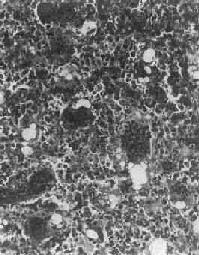

镜下,肿主要由单核基质细胞及多核巨细胞等两种细胞组成(图17-6),间质血管丰富。基质细胞为梭形、卵圆形或圆形,细胞境界不清楚,常见胞浆突起。细胞核较大,染色质量中等,可具有一个核仁。多核巨细胞常较均匀地散布在基质细胞之间,是为本的特点。多核巨细胞的直径常为30~60μm,核数一般为15~20个,最多可达100个以上,常聚集在细胞的中央。核的形态与单核基质细胞相似。细胞边界不规则,但分界较清楚,胞浆丰富,略呈嗜碱性,有时还可见含大量脂类的泡沫细胞。本间质血管丰富,有多少不等的胶原纤维。肿本身无成骨现象,但有时见有类骨组织及新生骨小梁,常见于纤维组织的周围,可能是一种反应性新骨形成或病理性骨折后形成的骨痂。

图17-6 骨巨细胞(Ⅰ级)

由大量基质细胞和多核巨细胞两种细胞组成